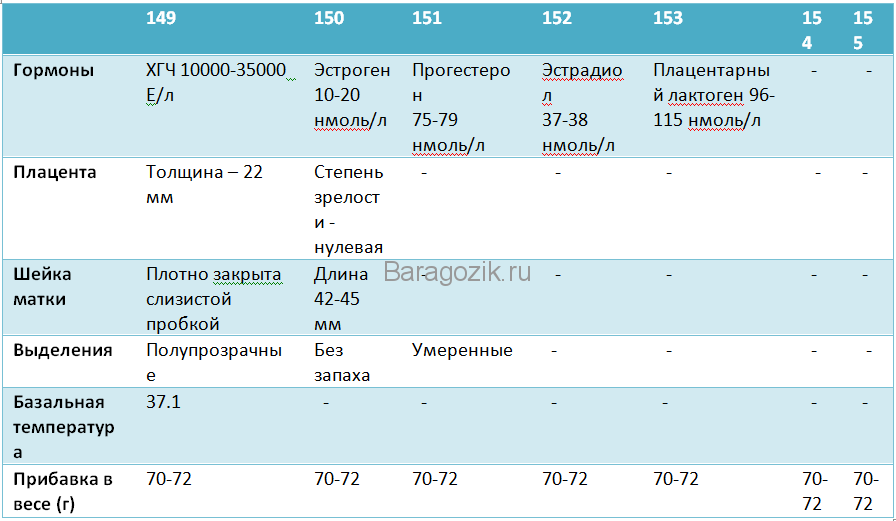

Анализы и обследования на 22-й неделе

Примерно 2–3 раза в месяц беременная посещает гинеколога. Накануне приёма она приносит пробы мочи в лабораторию женской консультации. Этот анализ позволяет:

- оценить уровень лейкоцитов;

- обнаружить белок для своевременного выявления сбоя в работе почек, воспалительных процессов.

При необходимости врач даёт направление на анализы крови, чтобы определить уровень гормонов, гемоглобина и т. д, рекомендует пройти другие внеплановые обследования. Так, если ранее был обнаружен конфликт по резус-фактору крови мамы и плода, регулярно назначается обследование на выявление специфических антител — гемолизинов, которые могут попасть в организм плода через плаценту. Впоследствии новорождённый может болеть желтухой, нуждаться в переливании крови. Из-за резус-конфликта иногда происходят преждевременные роды.

Если есть опасность развития резус-конфликта, женщине регулярно назначают анализ крови на антитела

На каждом приёме доктор:

- взвешивает пациентку;

- измеряет объём её живота;

- осматривает кожные покровы, конечности на предмет отёков;

- измеряет артериальное давление;

- определяет высоту дна матки;

- прослушивает сердцебиение плода;

- оценивает результаты анализов;

- назначает приём медикаментов при необходимости.

Что определяют на УЗИ

На 22-й неделе проводится второе скрининговое УЗИ, если оно не было назначено немного раньше. В отличие от первого скрининга, сейчас анализы крови не являются обязательными, если в прошлый раз не было выявлено риска рождения ребёнка с аномалиями развития. В ходе исследования врач определяет положение малыша в утробе. Оно может быть:

Нормальными считаются следующие показатели:

- БПР (бипариетальный размер, измеряемый от одного до другого виска головы) – 48–60 мм;

- ОГ (окружность головы) – 64–76 мм;

- ОЖ (окружность живота) – 148–190 мм.

Оценивается также состояние матки на предмет тонуса, состояние и расположение плаценты, степень её зрелости

Немаловажное значением имеет количество околоплодных вод